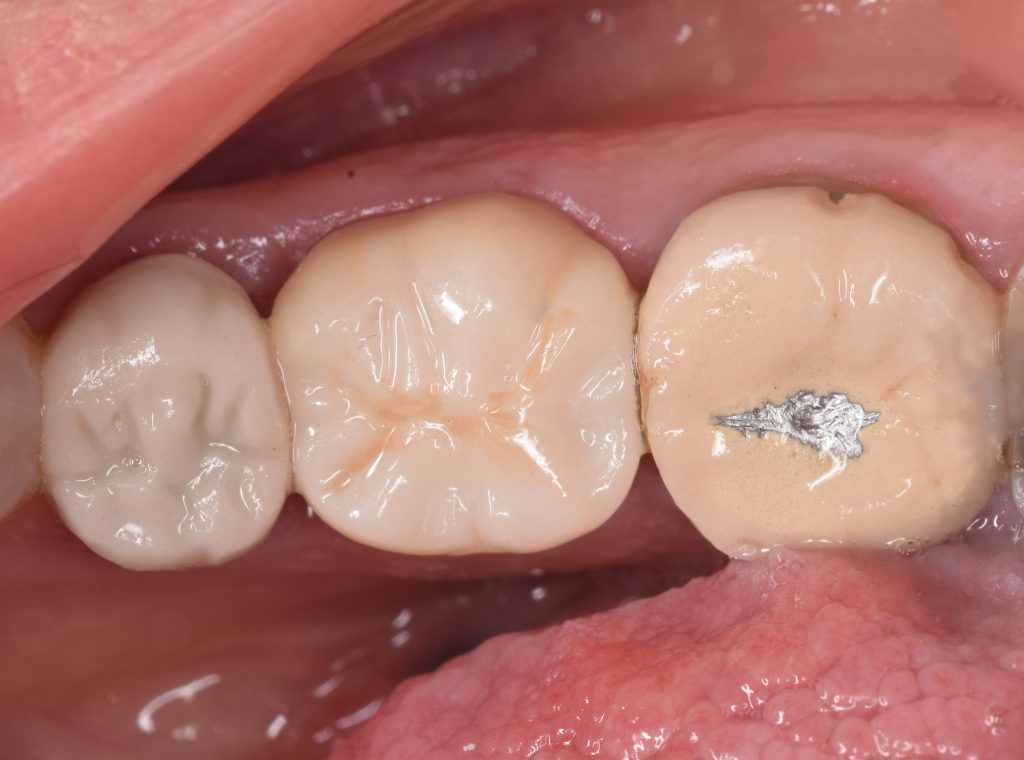

Good prep and zirconia crown placed